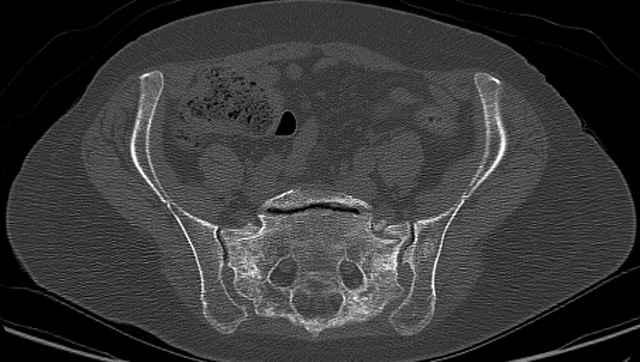

Pelvic CT Scan - 3 Months After Fall

Sacral Injuries

Ramus Fractures

Percutaneous Fixation

(B) Ramus-Retrograde

2 TransIliac-TransSacral

Upper Segment